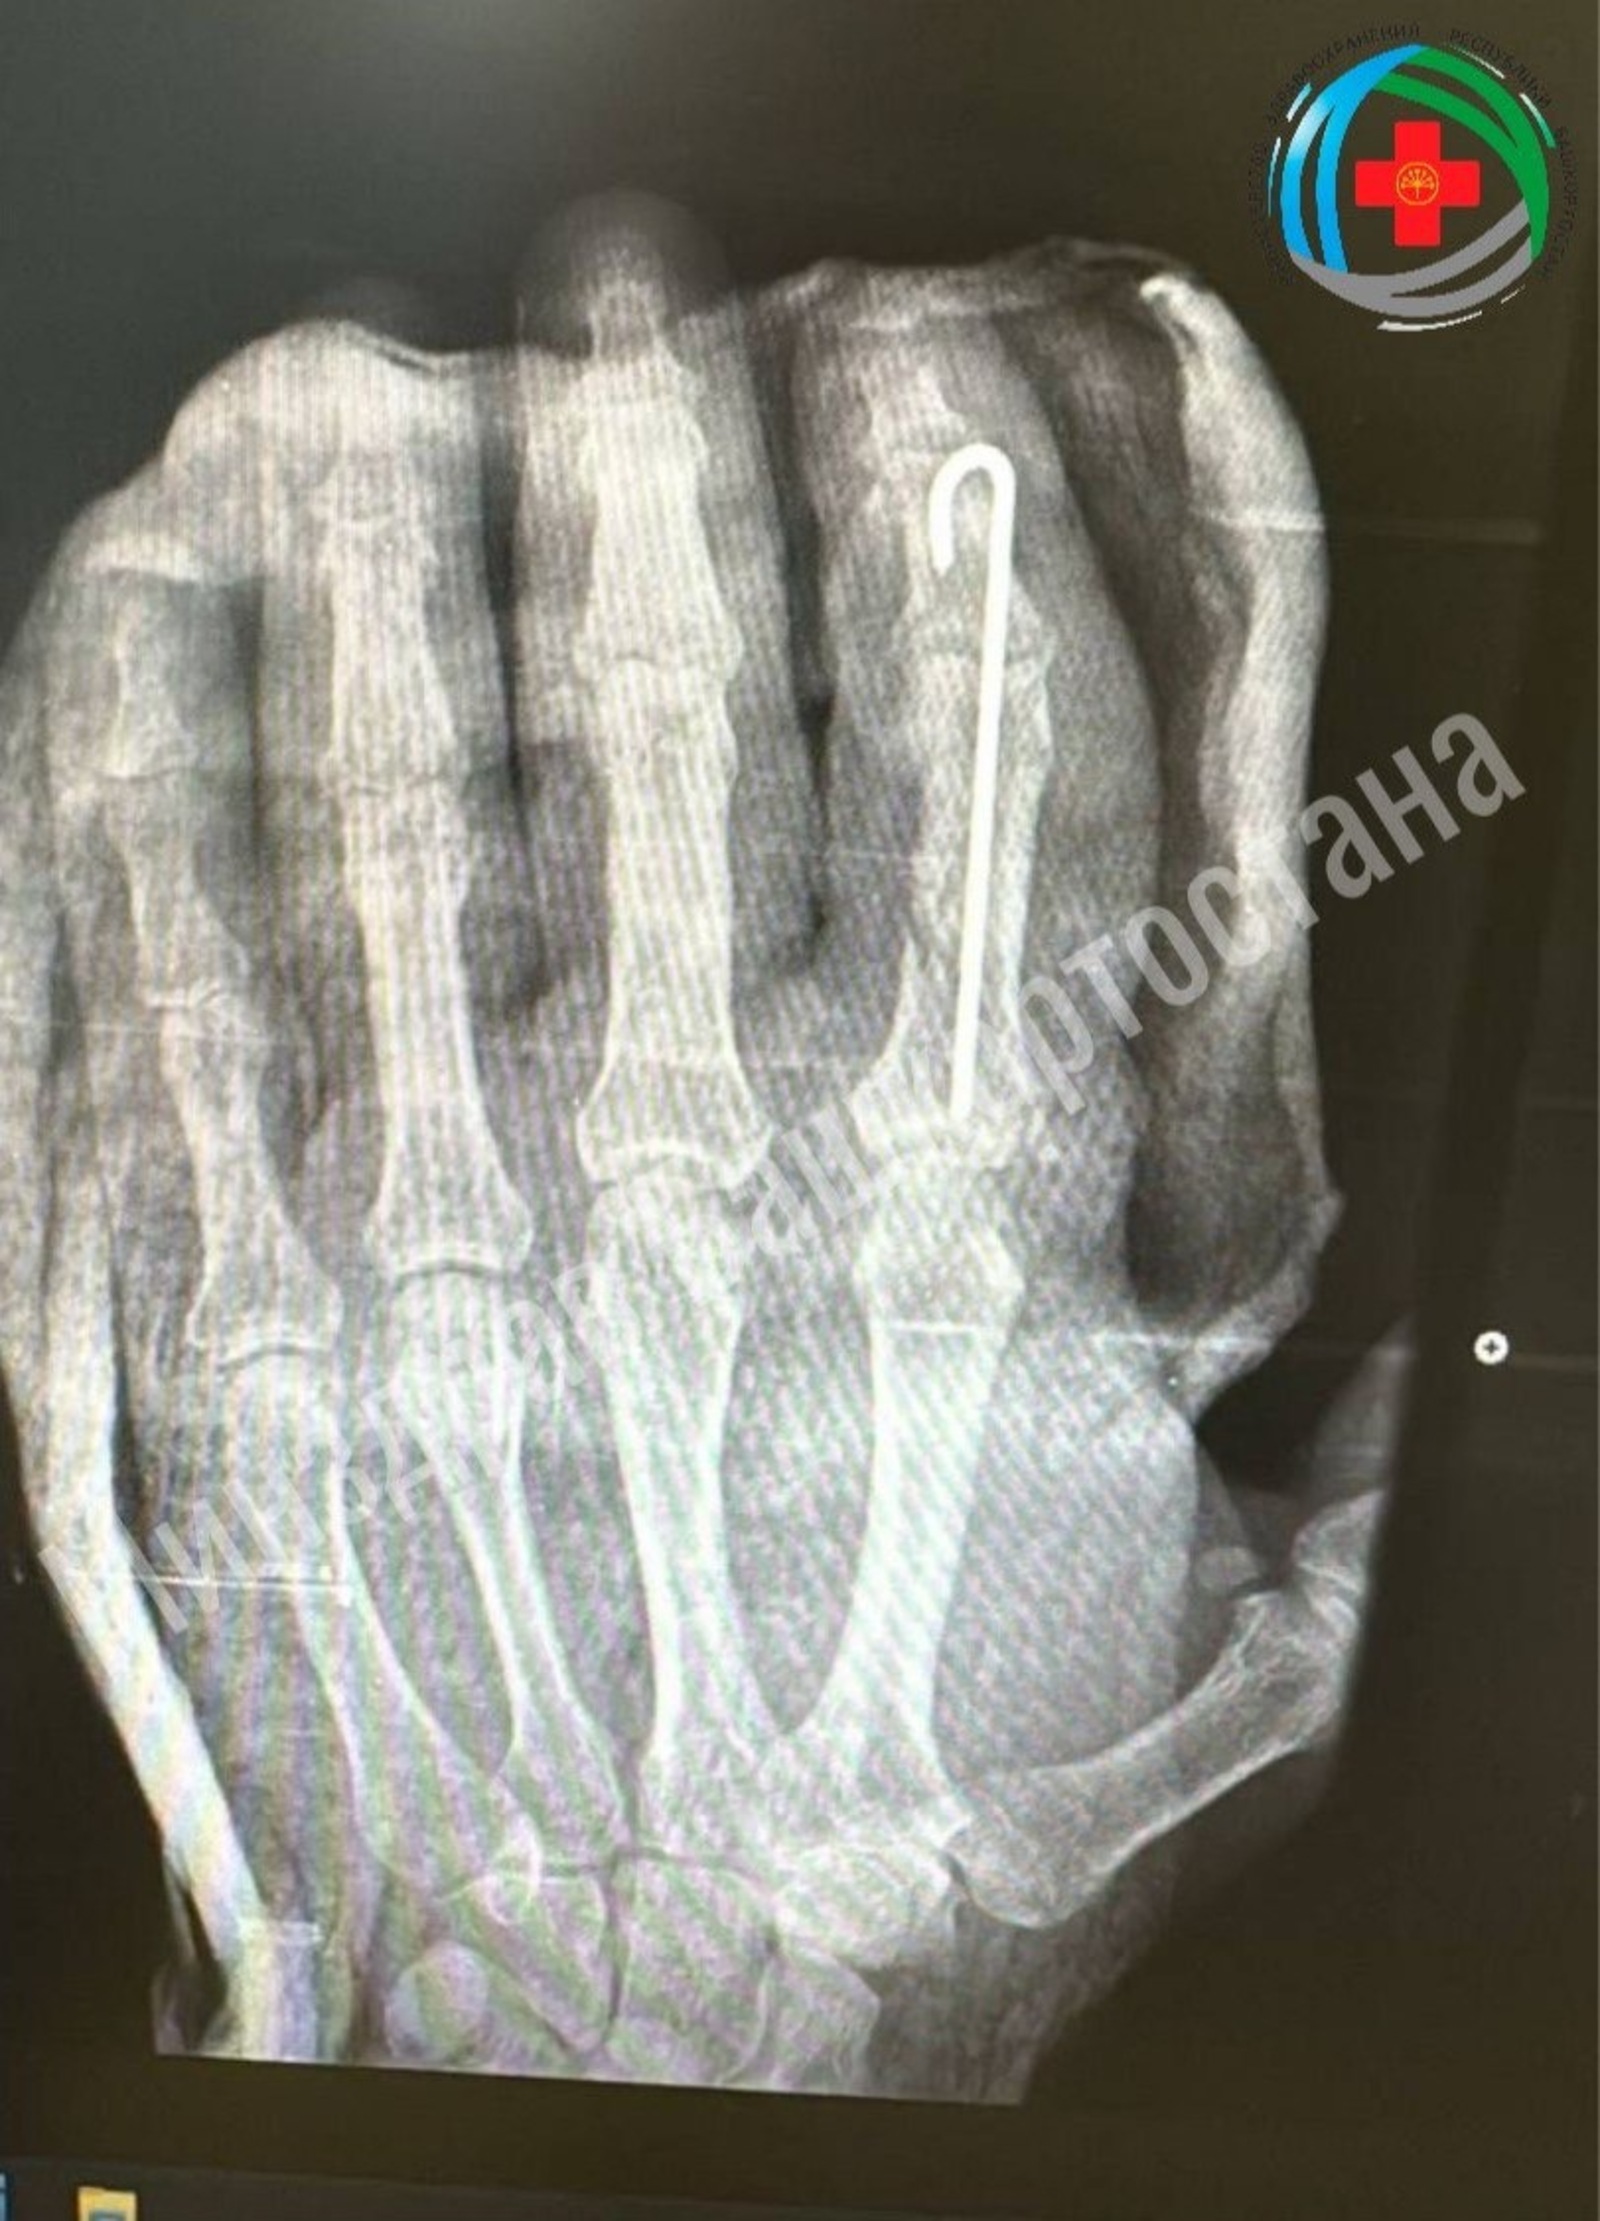

Врачи экстренно прооперировали его, проведя сложнейшую операцию: они восстановили крошечные сосуды, кость и ткани.

В минздраве региона сообщили, что операция прошла успешно, палец прижился. Пациент уже начал двигать им и проходит курс реабилитации, который включает физиотерапию и ЛФК. Ожидается, что после восстановления функции пальца вернутся полностью.